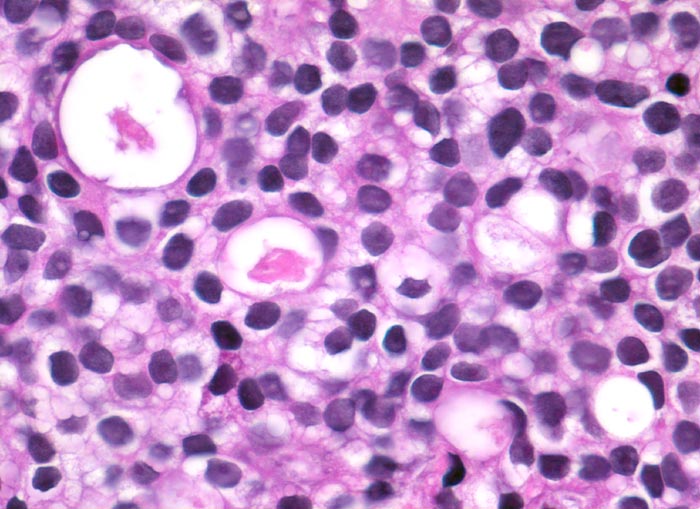

Prostatakarzinom

maligner Tumor

Prostata

Monomorpher kribriformer Tumor bestehend aus kleinen Tumorzellen mit rundlichen Kernen mit promimenten Nukleolen.

St.n. Bestrahlung eines Prostatakarzinoms. Jetzt Tumor in der Harnblasenwand.

400